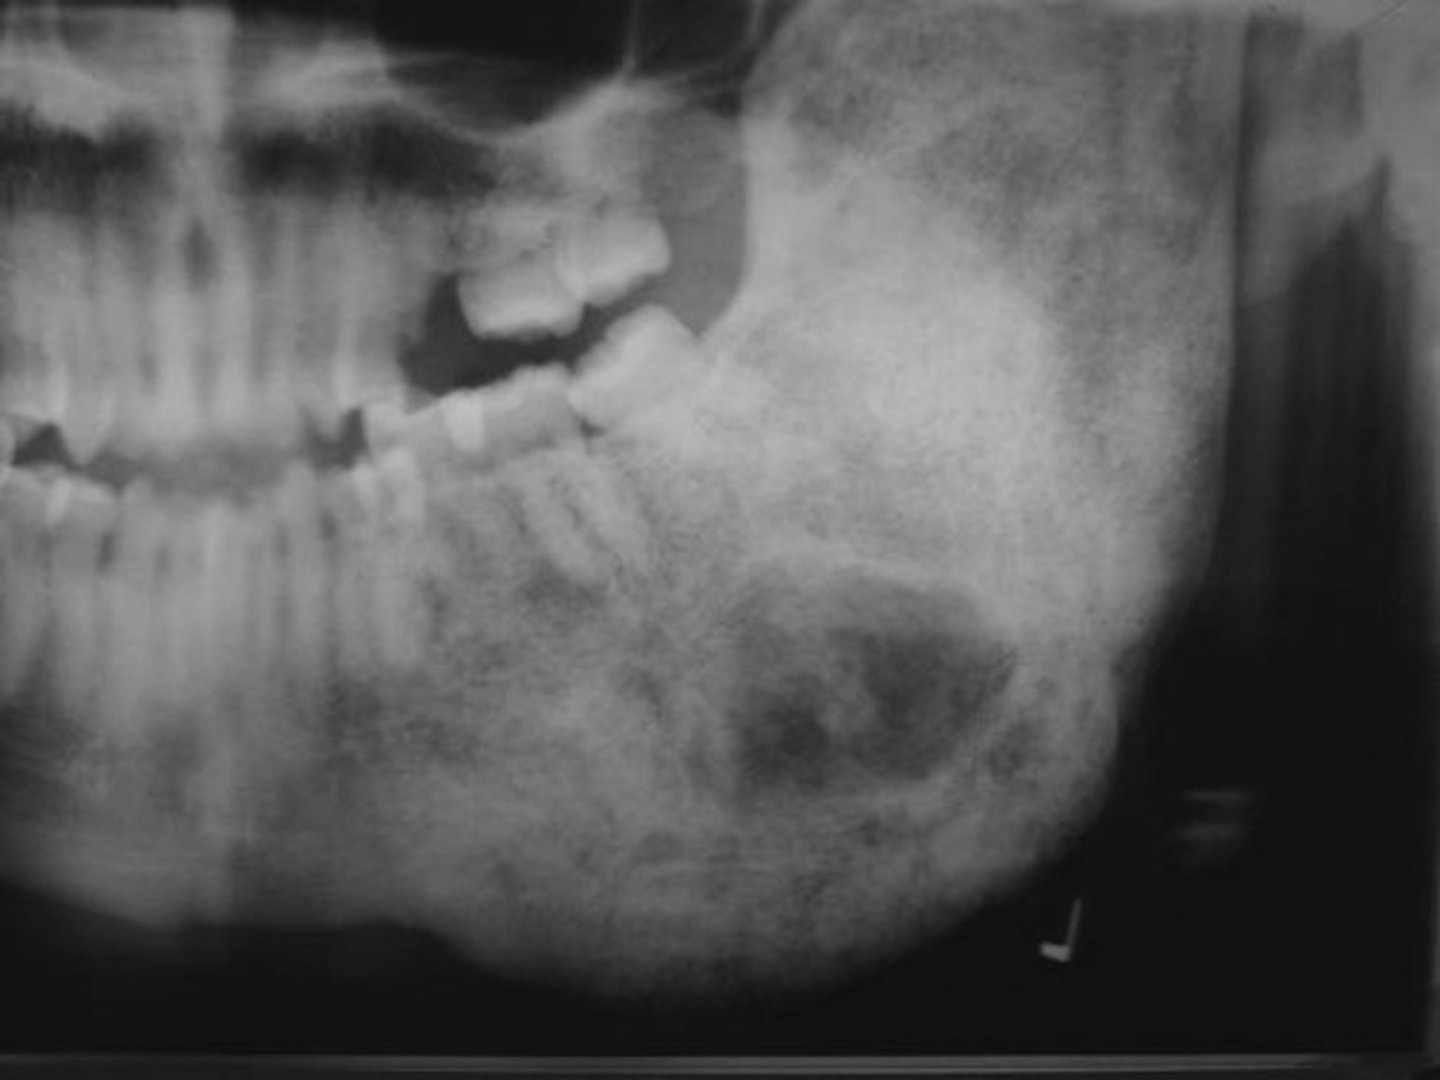

Aneurysmal Bone Cyst

reactive lesion of bone

exaggerated, localized proliferative response of vascular tissue in bone

Clinical Features of Aneurysmal Bone Cyst

under 30

predilection females

rapid bone swelling

pain

tender on palpation

Location of Aneurysmal Bone Cyst

mandible

Periphery of Aneurysmal Bone Cyst

well-defined

Internal structure of Aneurysmal Bone Cyst

multilocular